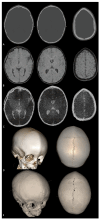

Craniosynostoses (CRS) are caused by the premature fusion of one or more cranial sutures, with isolated nonsyndromic CRS accounting for most of the clinical manifestations. Such premature suture fusion impacts both skull and brain morphology and involves regions far beyond the immediate area of fusion. The combined use of different neuroimaging tools allows for an accurate depiction of the most prominent clinical-radiological features in nonsyndromic CRS but can also contribute to a deeper investigation of more subtle alterations in the underlying nervous tissue organization that may impact normal brain development. This review paper aims to provide a comprehensive framework for a better understanding of the present and future potential applications of neuroimaging techniques for evaluating nonsyndromic CRS, highlighting strategies for optimizing their use in clinical practice and offering an overview of the most relevant technological advancements in terms of diagnostic performance, radiation exposure, and cost-effectiveness.